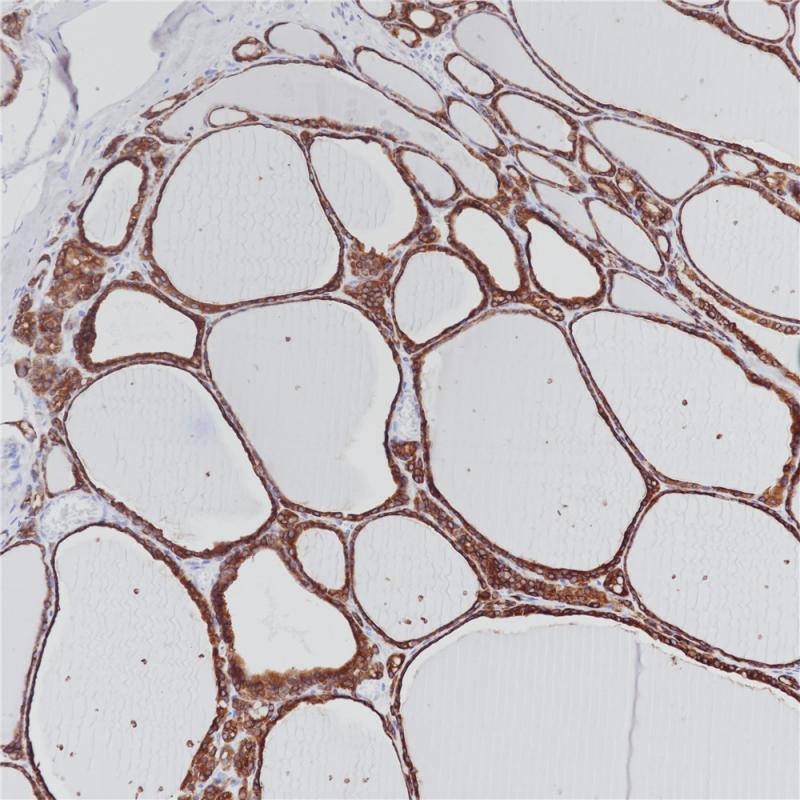

TPO(甲状腺过氧化物酶)在甲状腺细胞的顶端表达,是一种与甲状腺激素合成相关的酶。TPO可以在正常甲状腺、甲状腺滤泡以及树突状癌中表达,通常作为甲状腺肿瘤良恶性的鉴别手段。

阳性对照

甲状腺

亚细胞定位

细胞质